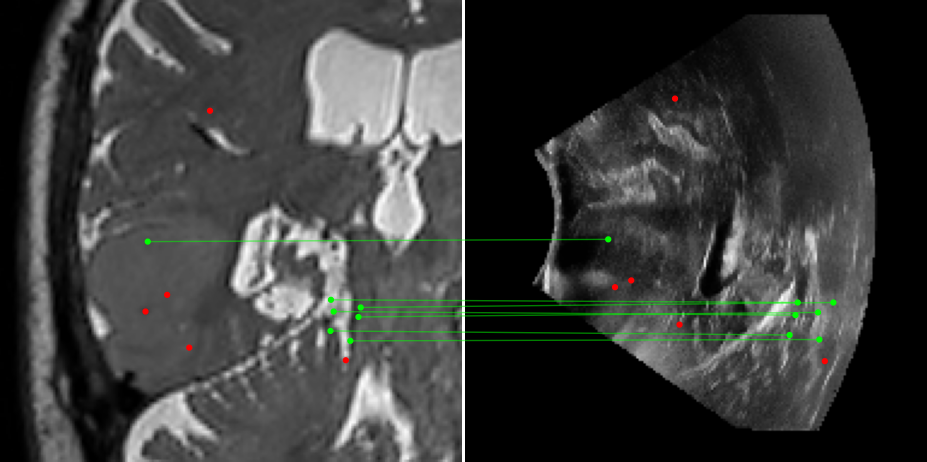

Figure 3: Examples of matching on three cases, one per column (MR on left and US on right). From top to bottom: SIFT+Cosine, MIND+Cosine, SP+Cosine, SP+LG, Ours+LG, Ours+Cosine. Correct matches recovered by each method are shown in green lines and mismatched are shown with a red dot.

To evaluate the performance of our model against existing image methods, we compared it to three approaches: SIFT [16], which remains the standard for keypoints matching, SuperPoint (SP) [3] built using a self-supervised learning approach and MIND [10], a modality-invariant descriptor for medical imaging, that although not designed for 1-to-1 keypoint matching, is extensively used for multimodal medical image registration through grid regularizing. We use SIFT and SP as keypoints detectors and descriptors, while we combine MIND with SP keypoints since it only provides a descriptor. We match these descriptors using both Cosine similarity and the deep neural network LightGlue (LG) [15] when possible (SP and Ours). Results reported in Table 2 and shown in Fig. 3 show that our approach outperforms these methods in terms of matching score, precision, and number of matched points. We only report results on three cases for readability reasons. Associating our descriptor with Cosine and LG reached similar performance depending on the metric.